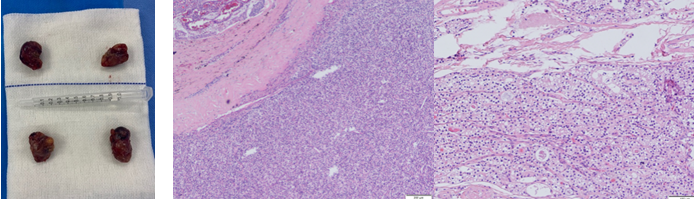

患者基础疾病较多、营养状况差,麻醉科高度重视,潘振祥主任亲自主持会诊,严密制定麻醉和应急方案。在麻醉科的紧密配合下,张弘教授为患者进行手术治疗,术中发现四枚增大的甲状旁腺并全部切除,术中病理证实其均为增生的甲状旁腺组织。术后患者拔管清醒抵达ICU,观察一夜病情稳定。术后第1天,患者的骨痛症状“神奇”地消失了。随后,患者安返肾病内科病房,经过肾病内科的精细治疗,患者已可离床活动,顺利出院。至此,一场以病人为中心的多学科治疗顺利完成。在术后随访的1年中,患者恢复良好。